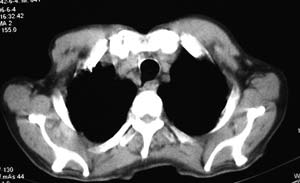

右侧胸廓略小于左侧,右肺上叶大片实变影,近肺门处密度较高,内见支气管气相,周围较淡,呈网格状,余肺野清晰,纵隔内见肿大淋巴结,右侧胸腔少量积液。临床 咳血,咳痰 发热 , 血象1.2万。

影像表现:肺窗示右肺上中叶均可见小片、条索状、小结状密度增高影,可见支气管充气相,小叶间隔增厚,支气管通畅,余肺未见明显异常。纵隔窗示4r可见小淋巴结融合,无明显肿大,右侧示少量胸腔积液。

男 64  咳血,咳痰 发热 3天 血象1.2万;右肺上叶满布片絮状致密灶,其内见含气支气管影,右主支气管狭窄,纵隔内见肿大淋巴结。考虑右肺中央型肺癌伴阻塞性肺炎,建议支气管镜检查。